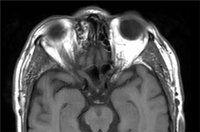

La determinación de hormonas tiroideas y anticuerpos anti-tiroides (anti-tiroglobulina y anti-peroxidasa) resultaron normales y negativos respectivamente. La tomografía computerizada (TC) de órbita no mostró engrosamiento ni asimetría de las dimensiones de los músculos extrínsecos oculares. Se observaron unas alteraciones en el ángulo superointerno del marco óseo de la órbita derecha

(Figura 3a y

Figura 3b) que involucraban múltiples huesos y se sugirió el diagnóstico de displasia fibrosa poliostótica. En la

Figura 3a. TC órbita: Lesión en el ángulo superointerno de la órbita derecha con zonas hipodensas moteadas, con posible crecimiento intracraneal. Destaca a nivel del hueso frontal derecho, un engrosamiento óseo que ocupa parte del seno frontal ipsilateral y celdillas etmoidales anteriores derechas. En su interior se identifican zonas de esclerosis. Deforma discretamente el techo de la órbita derecha.

Figura 3b. RM T1 axial con contraste. La musculatura extrínseca ocular de la región (oblicuo superior) queda incluida en las alteraciones óseas lo que condiciona una restricción del la polea y el cuadro de síndrome de Brown adquirido.